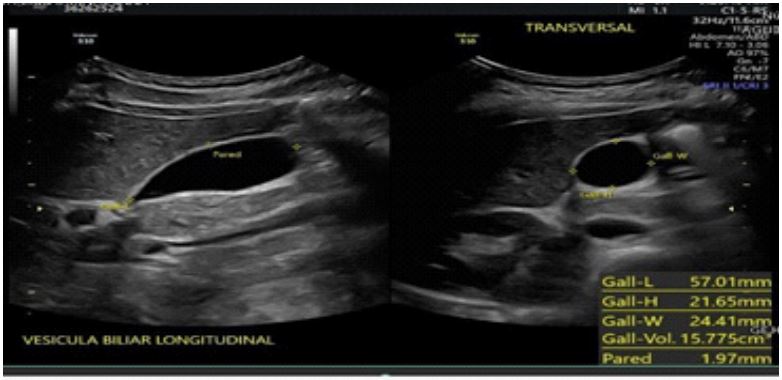

Radiological description

- Liver: Normal contours and echogenicity, homogeneous ultrasound pattern, no intrahepatic bile duct dilation.

- Common bile duct: 1 mm diameter, portal vein: 6.8 mm diameter.

- Gallbladder: Normal shape and contours, dimensions 51x20x24 mm (longitudinal, anteroposterior, transverse), wall thickness 2.4 mm. An intravesicular image was observed: anterior wall hyperechoic, homogeneous, solid, regular contours, no color Doppler flow, immobile, measuring 2.9 mm.

Conclusion: Small polyp inside the gallbladder, echogenic linear image compatible with a nematode, probable biliary ascariasis (Figure 1).

Figure 1: Ultrasound image of biliary ascariasis.